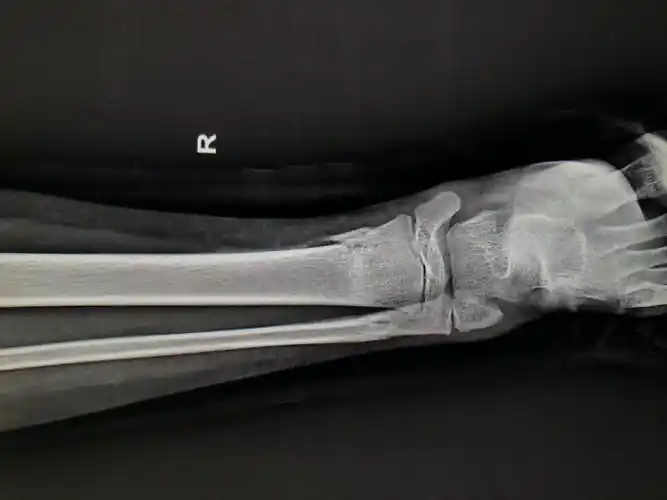

梁司晨,10岁,右胫腓骨骨折